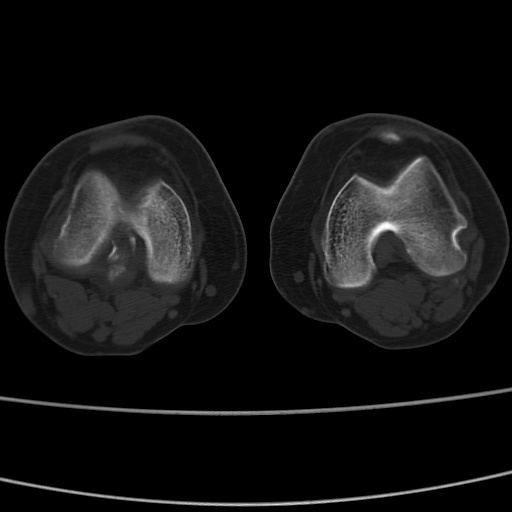

女性,50岁。【请提供患者临床症状体征】

右膝关节退行性改变,关节游离鼠。

右膝关节退行性改变,滑膜黏液囊钙/骨化并游离。